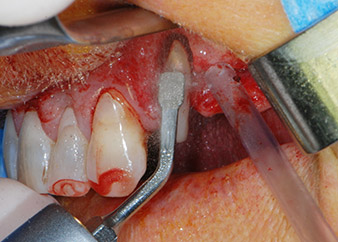

One month later, on the day of surgery, pain and inflammation at tooth 24 were minimal, but mobility of Miller class 2 was still present. After opening the flaps and cleaning the periapical and peri radicular infected tissue, the extent of the bone defect became obvious (Figs. 2 and 3).

At the buccal root, all vestibular and distal bone was missing. Attachment was essentially restricted to the palatal root, underlining the preliminary poor prognosis. Tooth 27 also showed a reduced horizontal attachment and a minimal apical rarefaction (cf. Fig. 1) without clinical symptoms.

total loss of bone and attachment

Fig. 2 and 3: After raising flaps, one month after endodontic revision and initiation of full-mouth periodontal therapy, the buccal root of tooth 24 showed a total loss of bone and attachment.

However, we maintained our initial plan to retain both teeth as temporary bridge abutments during the six-months osseointegration period of the implants. At reentry, the situation would have to be reassessed. First, in an attempt to manage the endo-perio problem, the remaining root surface was carefully debrided with piezoelectric equipment (Piezomed, W&H, used with the spatula-shaped insert S1, originally designed for erosion of the lateral sinus wall) (Fig. 4).

Then the apex was abraded with the same instrument to remove residual infected apical tissue and to reduce possible accessory root-canal ramifications (apicoectomy) (Fig. 5). A retrograde filling was not necessary because the orthograde filling had just been revised.

periodontium

Fig. 4: To preserve the tooth as a temporary abutment, the periodontium was debrided with piezoelectric equipment …

buccal apex of tooth 24

Fig 5: ... and the buccal apex of tooth 24 was abraded with the same instrument (apicoectomy).